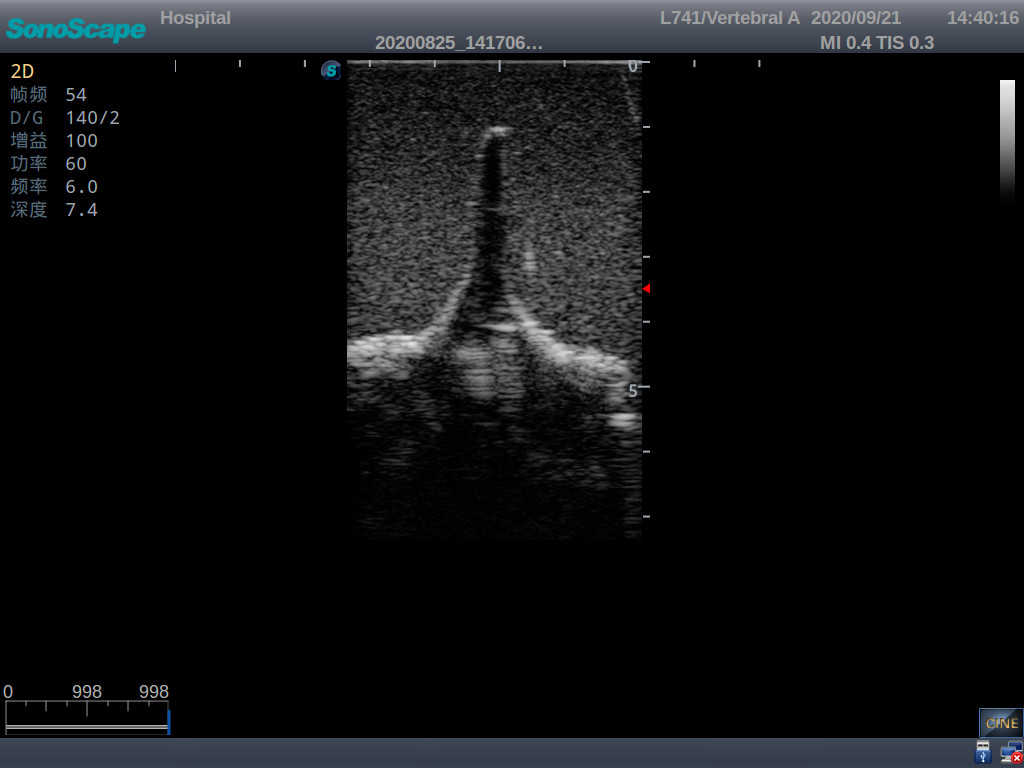

Adult Lumbar Puncture Ultrasound Training Model

Model TYE1549.2

This model is an ideal choice for ultrasound-guided adult lumbar puncture training with true-to-life skin feel and touch, accurate anatomical structures as well as real clinical ultrasound images. Realistic resistance to needle tips and correct landmarks provide excellent hands-on experience.

Accurate anatomical structure of L1-L5 and the vertebral canal

2)  Real clinical ultrasound images

3)  Compatible with various real ultrasound machines